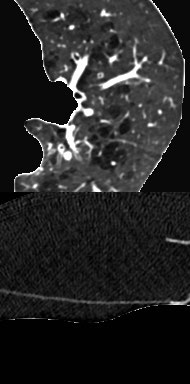

Reliably detecting diseases using relevant biological information is crucial for real-world applicability of deep learning techniques in medical imaging. We debias deep learning models during training against unknown bias - without preprocessing/filtering the input beforehand or assuming specific knowledge about its distribution or precise nature in the dataset. We use control regions as surrogates that carry information regarding the bias, employ the classifier model to extract features, and suppress biased intermediate features with our custom, modular DecorreLayer. We evaluate our method on a dataset of 952 lung computed tomography scans by introducing simulated biases w.r.t. reconstruction kernel and noise level and propose including an adversarial test set in evaluations of bias reduction techniques. In a moderately sized model architecture, applying the proposed method to learn from data exhibiting a strong bias, it near-perfectly recovers the classification performance observed when training with corresponding unbiased data.

翻译:利用相关的生物信息可靠地检测疾病对于医学成像中的深层学习技术在现实世界中的适用性至关重要。我们在针对未知偏差的训练中贬低深深学习模式----不事先处理/过滤输入,也不假定对数据集的分布或确切性质有具体了解。我们使用控制区域作为代理机器人,提供与偏差有关的信息,使用分类模型提取特征,并按我们的习惯,即模块化的德科勒拉耶来抑制有偏见的中间特征。我们通过引入模拟偏差重建内核和噪音水平来评估952个肺部计算断层扫描数据集的方法,并提议在对减少偏差技术的评价中包括一个对立测试组。在一个中小的模型结构中,采用拟议的方法从显示强烈偏差的数据中学习,它几乎完全恢复了在用相应的不偏差数据进行培训时观察到的分类性能。